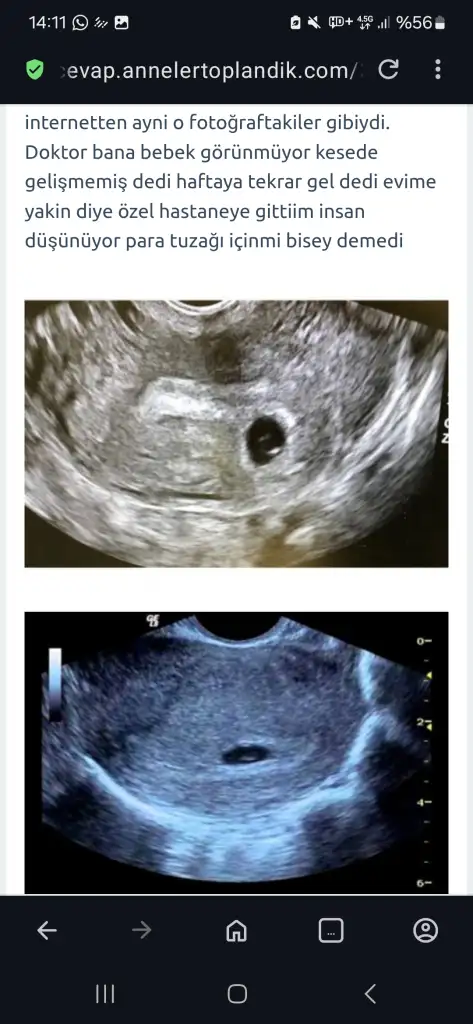

Hayırlısı inşallah kanlar nasıl negatif çikar hayret. Yani bu da bariz kese bence kiste filan benzemiyo gibi.Hatta özelden randevu aldım az önce gidiyorum bakalm orda ne cikcak